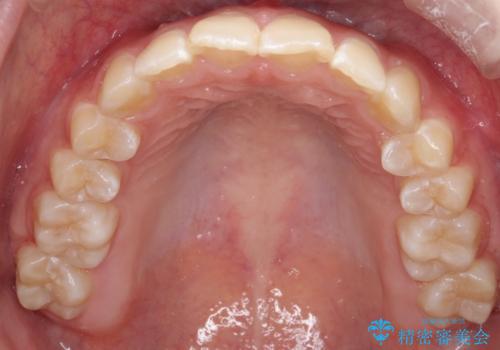

- 前歯が出ていることを主訴に来院されました。

インビザラインにて奥歯の遠心移動を行いながら最大限前歯が下がるように治療を行いました。

今回は遠心移動とIPRによってここまで前歯を下げることができました。